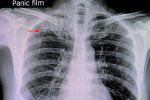

Antibiotika-Tests haben eine Schwachstelle, die eine neue Erkennungsmethode umgehen könnte: Bakterien werden gefilmt, um zu prüfen, ob ein Mittel sie wirklich abtötet